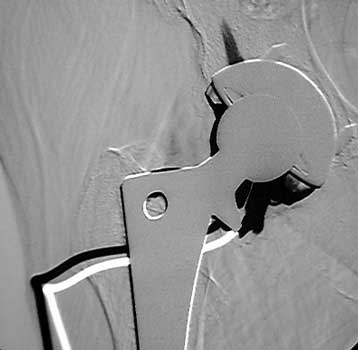

Arthrographic evidence of loosening—contrast enters

abnormally widened interface Gruen zone 1 and 2

Arthrographic evidence of cup loosening—contrast enters

abnormally widened interface Gruen zone II and III